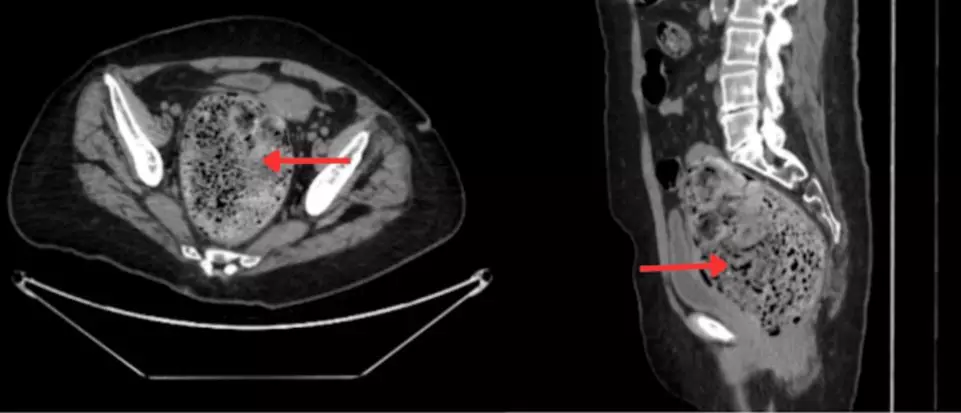

CT(컴퓨터단층촬영) 검사 결과, 직장과 연결된 대장 아랫부분인 S자 결장에 최대 12.2×10.5cm 크기의 거대한 분변종이 발견됐다. 분변종은 장 속에서 장기간 머문 대변이 수분을 잃고 돌처럼 딱딱하게 굳어 덩어리 형태로 변한 상태를 말한다. 심한 경우 석회화가 진행돼 엑스레이나 CT 상에서 종양처럼 보이기도 하며, 장폐색, 분변성 궤양, 천공, 요폐 등 심각한 합병증으로 이어질 수 있다. 일반적으로는 경구용 완하제, 관장, 수동 제거 등의 보존적 치료를 우선 시행하며, 효과가 없을 경우 내시경이나 수술적 치료가 필요하다.

입원 13일째, 증상이 개선되지 않자 의료진은 대체 치료로 ‘코카콜라 관장’을 시도했다. 1000mL의 일반 코카콜라를 관장액으로 투여한 결과, 다음날 복통과 구토 증상이 사라졌고 CT 검사에서 분변종의 크기가 약 50% 감소한 것으로 확인됐다. 이후 입원 16일째 동일한 치료를 한 차례 더 시행하자 증상은 완전히 해소됐고, 환자는 유지 치료를 받은 뒤 퇴원한 것으로 전해졌다.